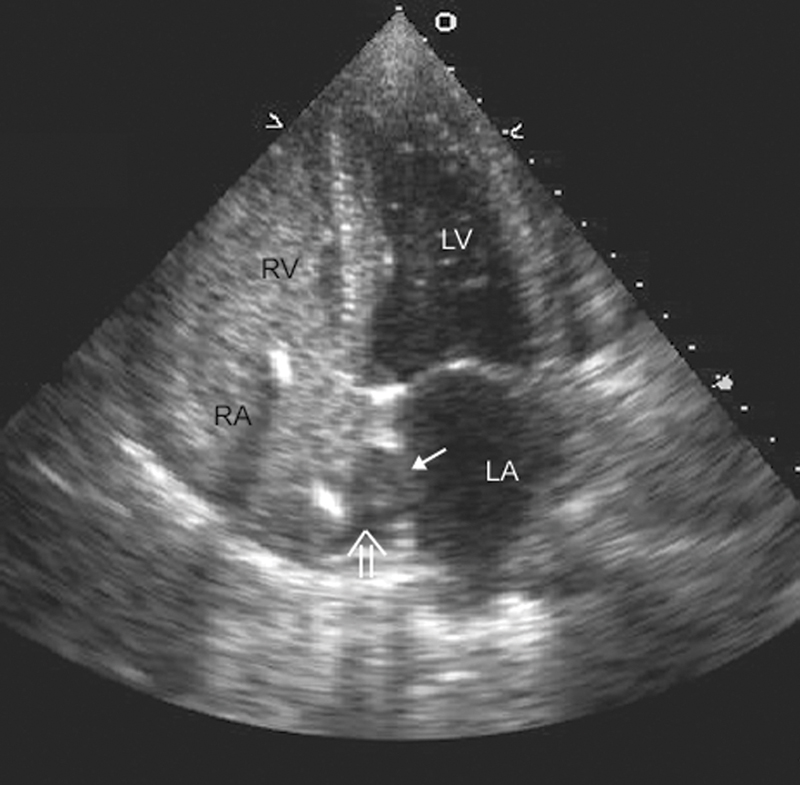

فحوصات تشخيصية لبعض امراض القلب والشرايين التاجية